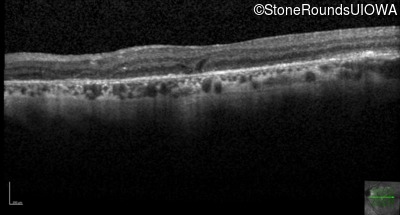

Age at visit: 57 years (Visit 2)